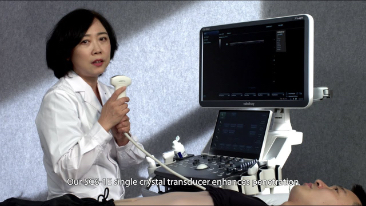

Kar??lanmayan klinik gereksinimlere ili?kin derin bilgisiyle Mindray, farkl? uygulamalarda daha hassas tan? ve gĂŒvenilir tedavi sa?laman?z i?in size kapsaml? g?rĂŒntĂŒleme ??zĂŒmleri sunmay? ama?lamaktad?r.